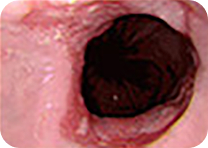

식도암

진행성 위암